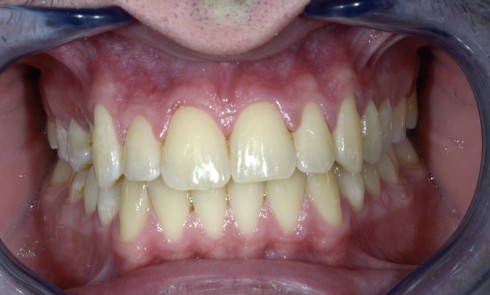

Article réservé à nos abonnés Classe III en fin de croissance

Rappel de la problématiqueGuillaume, 14 ans, se présente pour la première fois en consultation d’orthodontie, adressé par son dentiste. Il...